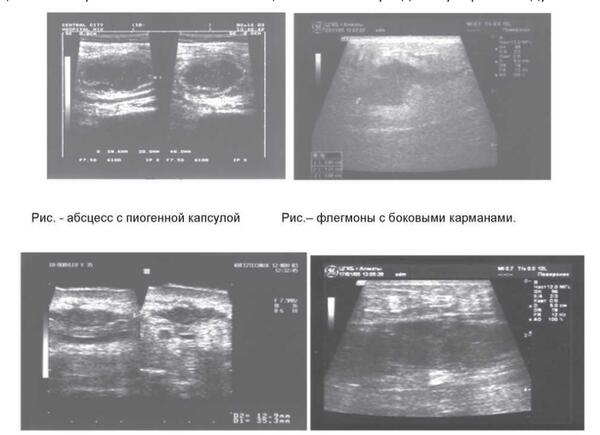

Периапикальный абсцесс мкб

Периапикальный абсцесс мкб 105 фото